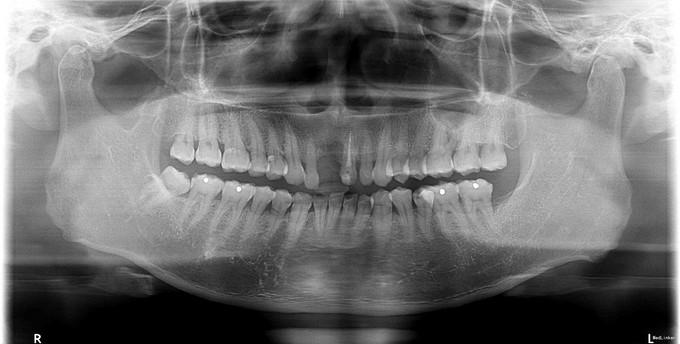

主诉:右上前牙缺失要求种植 现病史:患者诉右上前牙2月因外伤拔除,现为进一步治疗,遂到我院就诊

检查:右上后牙缺失,缺牙间隙正常,对颌无伸长,邻牙探-叩-松-,X片显示,缺牙处骨质稀疏 建议患者3月后复诊拍片